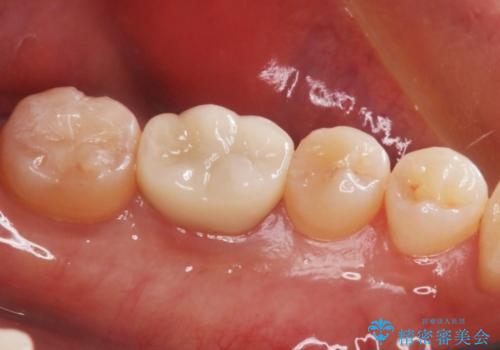

銀歯の下の虫歯|オールセラミッククラウン

担当医 河野豊嘉

奥歯に虫歯があると言われた セラミッククラウンでキレイで長持ちする歯へ

担当医 榊原康平